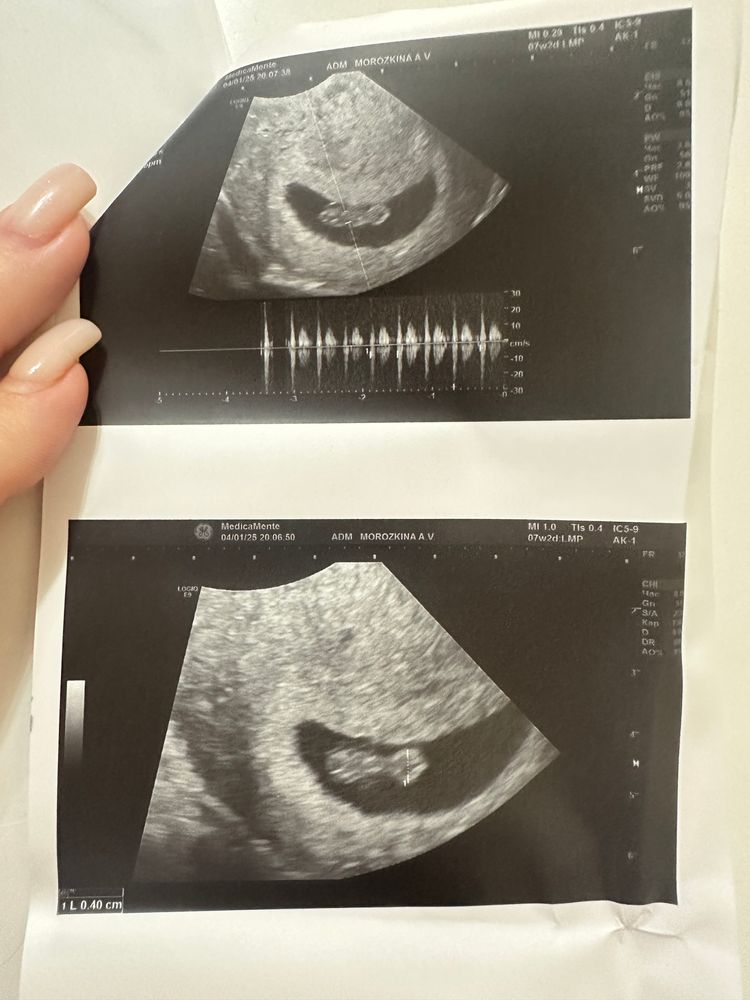

Вчера были на втором УЗИ.Наконец-то увидели наши полтора сантиметра счастья🥰🥰🥰Сердечку бьется,как сказал врач,тут и придраться не к чему,по УЗИ все отлично! Но как избавить себя от страха не представляю 🙈🙈🙈В 2020 году было прерывание по медицинским показаниям (Мегацистикс) по генетики все было хорошо и причину почему так случилось так никто не назвал.Сейчас жизнь круто изменилась,с первым мужем развелись, беременность от второго мужа, и больше всего страха вызывает возраст мужа (45 лет).Я безумно боюсь скрининга 🙈Врач сказал что нам надо идти через 4 недели,потому что мы опережаем срок.И чем скрининг ближе,тем большая паника меня охватывает.